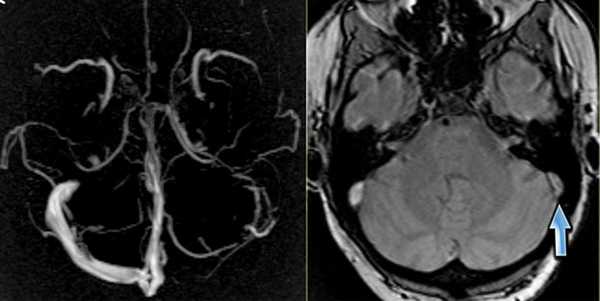

МРА-картина выраженной асимметрии венозной сети с преобладанием и нерезкой дилатацией вен правой гемисферы (поперечного, сигмовидного синусов и яремной вены справа); гипоплазии левого поперечного и сигмовидного синуса. Единичные участки (2) локального расширения вен в парасагиттальных отделах левой гемисферы, большой вены мозга. Асимметричная, расширенная и выражено извитая венозная структура экстракраниальных отделов справа.

МРА признаки незначительной дилатации верхнего сагиттального синуса, локального снижения кровотока и сужения просвета дистальных отделов прямого синуса; асимметрии просвета поперечных, сигмовидных синусов и внутренних яремных вен.

СОСУДИСТЫЕ МАЛЬФОРМАЦИИ

1. Венозная мальформация (венозная ангиома).

Встречается относительно часто и не является истинной мальформацией, в большей степени представляет собой вариант строения венозного оттока.

Течение обычно бессимптомное. Редко бывают судороги.

Венозная мальформация. Схема. Определяются мелкие расширенные венулы в виде «зонтика», «головы медузы», дренирующиеся в крупную транскортикальную вену, которая, в свою очередь впадает в верхний сагиттальный синус.

а) Т1 с внутривенным контрастированием. Стрелки показывают расширенные вены глубокого белого вещества, дренирующиеся в расширенную транскортикальную вену;

б) МР-венография с контрастированием показывает венозную дисплазию, дренирующуюся в расширенную внутреннюю мозговую вену. Венозная мальформация.